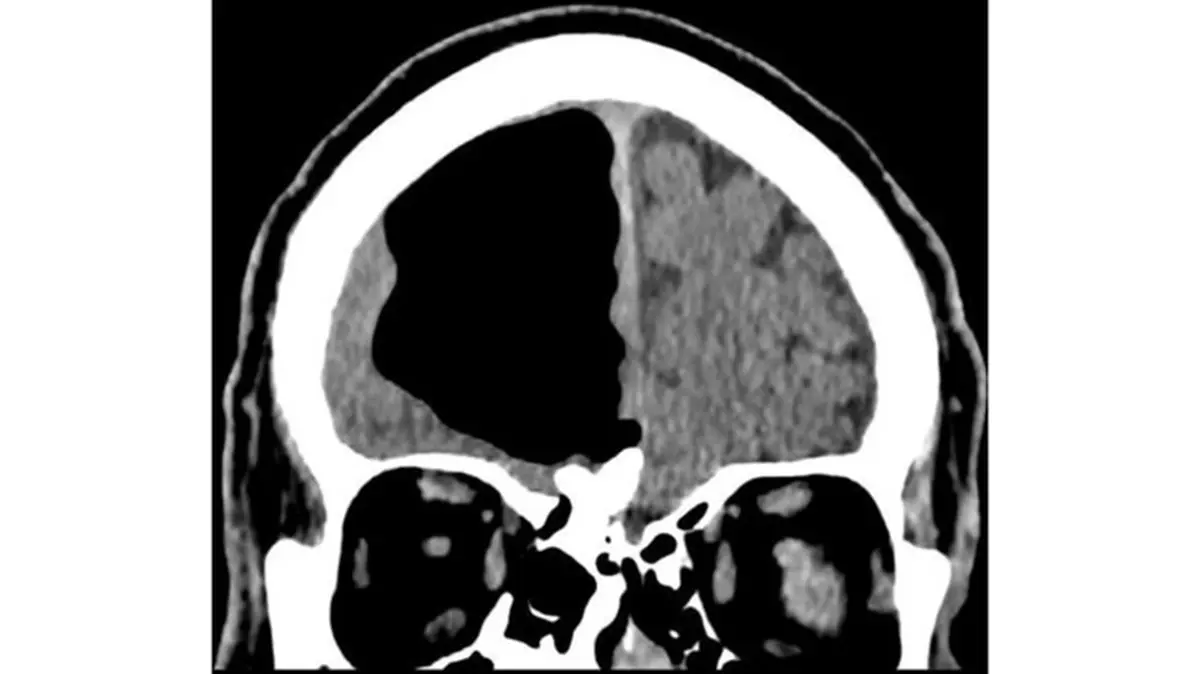

اگر چه نتیجه آزمایش خون این فرد طبیعی بود ولی تصویربرداریها از مغز او وجود یک حفره عجیب ۹ سانتی متری از هوا را در جمجمه نشان میداد.

این حفره به عنوان یک پنوماتوسل، حفرهای پرفشار از هوا، در سمت راست لوب پیشانی این فرد قرار گرفته است. این دسته از حفرهها معمولا در بیمارانی که سابقه جراحی مغز یا ابتلا به انواع مختلف عفونت را داشتهاند معمول است ولی اندازه آنها بسیار کوچکتر است.